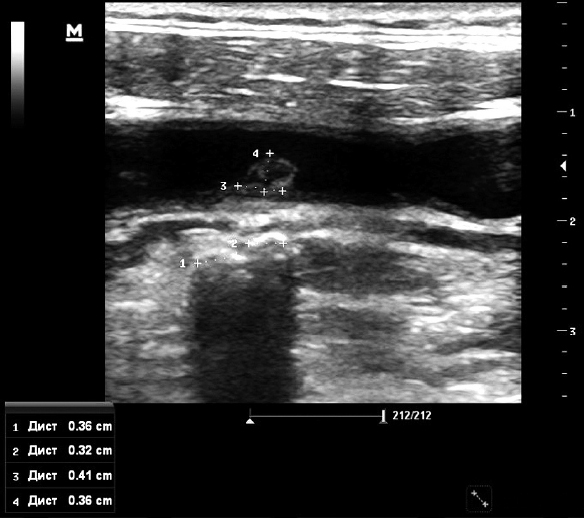

Clinical Case 1: a 63-year-old man with a mine-blast injury and shrapnel gunshot wounds to the head, neck, chest, abdomen, and extremities:

- Floating thrombus of the right common carotid artery (Figs. 3 and 4);

Fig. 3. Duplex ultrasonography of the cervical vessels. Foreign bodies (fragments and markers 1 and 2) adjacent to the posterior wall of the right common carotid artery. Floating intraluminal thrombus of the posterolateral wall of the middle third of the right common carotid artery (markers 3 and 4). Nonstenotic carotid atherosclerosis.